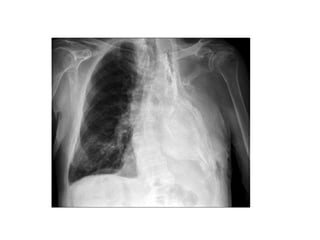

Thoracoplasty is a surgical procedure that involves removing parts of the ribs to collapse the chest cavity. It was historically used to treat tuberculosis and empyema but is now rarely used due to improved drug therapies. Indications for thoracoplasty include cavitary tuberculosis, empyema, and persistent spaces after lung resection. Complications include deformity of the chest wall and paradoxical breathing. Physiotherapy after thoracoplasty focuses on postural correction, breathing exercises, and preventing complications through exercise.